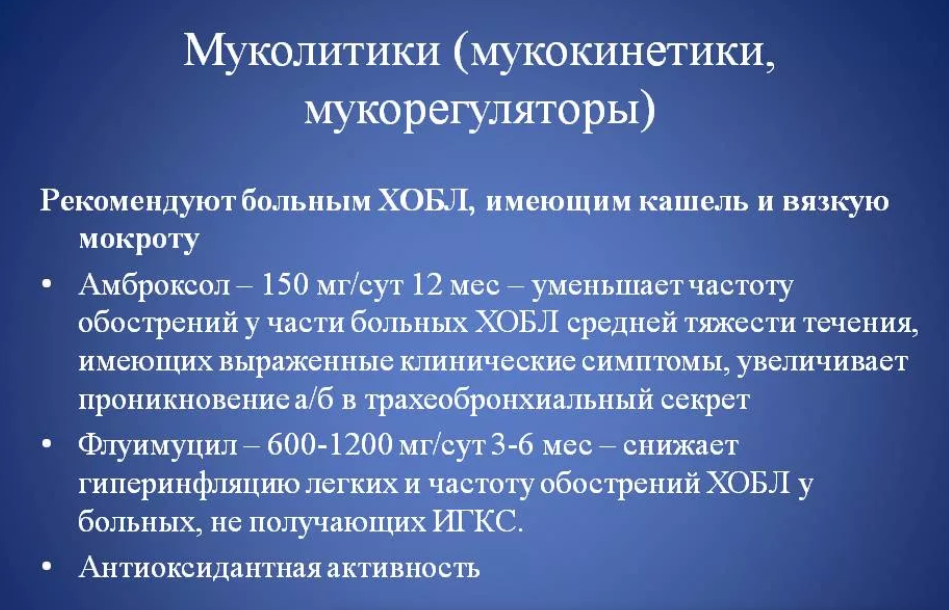

- Муколитики представлены обширной группой препаратов, в их числе – и знаменитый Бромгексин, Амброксол, Амбробене, Флуимуцил. При назначении лекарств из муколитических, учитывается характер заболевания и поставленный диагноз.